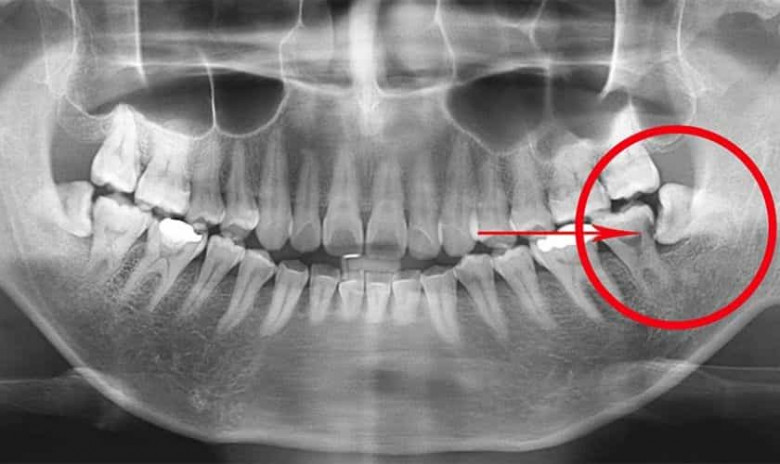

Ատամնաբույժների մեծ մասը խորհուրդ է տալիս հեռացնել իմաստության ատամնրը՝ դա հիմնավորելով, որ այդ ատամները պետք չեն:

Բժիշկ Ջեյ Ֆրիդմանի պնդմամբ՝ իմաստության ատամների երկու երրրոդը հեռացման կարիք չունի, հիվանդները կարգին վիճակում կլինեն, եթե պահպանեն այդ ատամները: